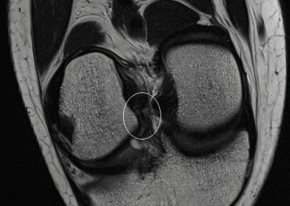

Das Team von MOTUM hat es sich zum Ziel gesetzt, alltägliche Bewegung bis hin zu komplexen Bewegungsabläufen des Spitzensports mit seinen Messmethoden sichtbar zu machen. Ziel ist es, individuellen Potentiale in der Bewegung zu erkennen und mögliche Schwächen aufzudecken, um Bewegung und Sport gesund und möglichst verletzungsfrei durchführen zu können. Die einzigartige Vernetzung mit Partnern…